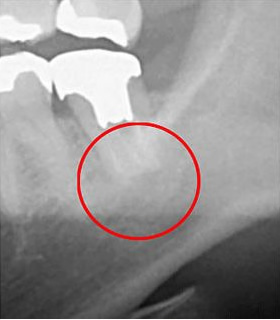

根管治療後に炎症が再発すると、歯の根の周囲に膿が溜まることがあります。症状の深刻さによっては、通常の根管治療では解決できず、抜歯が必要になる場合があります。

当院では、このような症例に対して「歯根端切除術」という手技を用いて治療を行います。歯根端切除術では、歯茎を切開して、炎症を引き起こした歯の根の先端と膿の袋を一体で除去します。手術後には空洞が残りますが、これは血液で満たされ、時間の経過とともに骨が再生します。